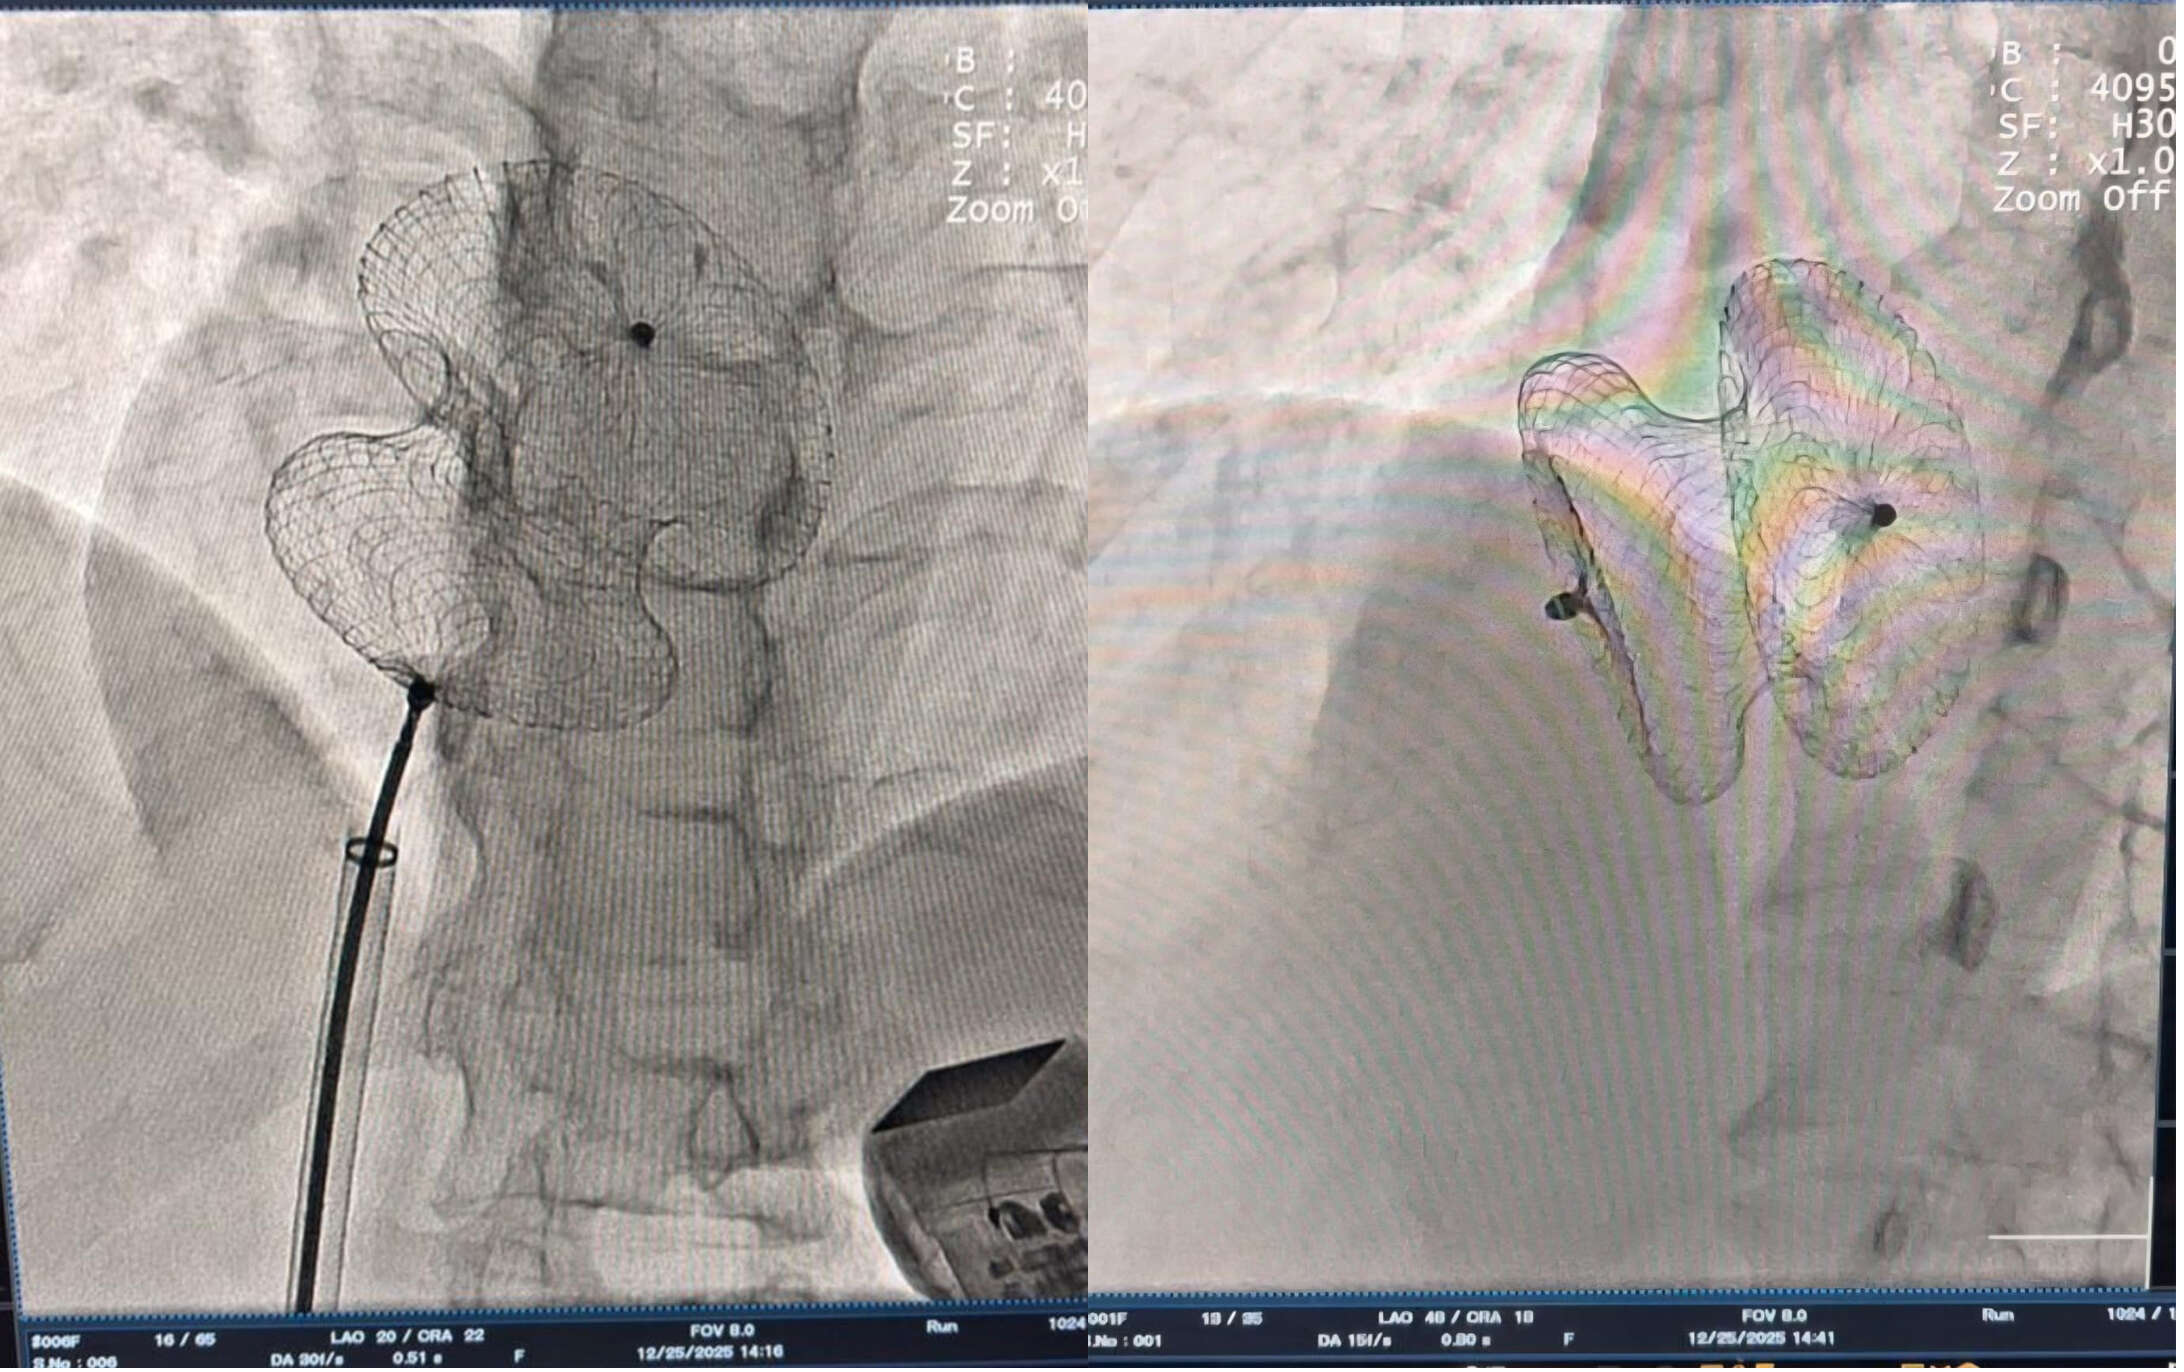

बिना चीर-फाड़ के 'डिवाईस क्लोजर' तकनीक का चमत्कार

परंपरागत रूप से, दिल के छेद को बंद करने के लिए 'ओपन हार्ट सर्जरी' करनी पड़ती थी, जिसमें छाती पर बड़ा चीरा लगाया जाता था और रिकवरी में महीनों लग जाते थे।

- मात्र एक छोटी डिवाइस: पैर की नस के जरिए एक विशेष डिवाइस (बटन जैसा) दिल तक पहुंचाया जाता है और छेद को प्लग कर दिया जाता है।